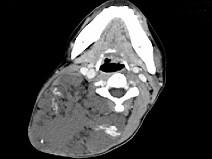

问题 女,32岁,颈部包块8年余,包块逐渐长大,CT如图所示,最可能的诊断为 ( )

选项 A、颈部神经鞘瘤 B、颈部异位甲状腺 C、颈部横纹肌肉瘤 D、颈部巨大血管瘤 E、颈部神经纤维瘤

答案 D